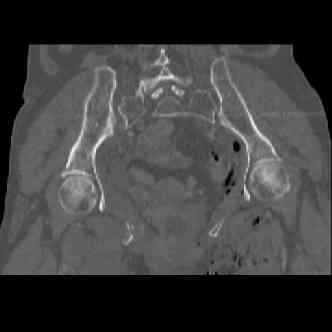

attached are images of a 70 year old female after peds versus car. her own car ran her over.

injuries are limited to the pelvis. left rami open and visible in a 10cm vertical laceration just lateral to left labia majora. wound is grossly clean. no vaginal and no urinary issues. CT scan shows widening of both SI joints anteriorly but I think this is vertically stable pattern.

pt treated that night with I/D and supra-acetabular frame to close the ring. consideration was given for SI screws bilateraly, but given time of night and other factors decision made not to proceed.

so the question is what next operatively if anything? concerns are infection, nonunion anteriorly and possible incompetence of the pelvic floor which may lead to prolapse issues. right rami are comminuted and plating may entail ilioinguinal approach to extend plate laterally to right iliac wing. retrograde screw up right rami is an option but I am not convinced it will add much. adding SI screws very doable, but major concern is restoring anterior ring. so far wound is clean and closed over a drain, and I have no plans to open it back up and wash again.

maintaining pelvic alignment in ex-fix in 70 yo female for any length of time may be challenging.

any thoughts? would anyone plate the pubic symphysis to close the gap and leave the more lateral rami fractures alone? the most recent pelvic case on this website involved pts with suprapubic catheters and antibiotic options including resorbable beads. I wonder how many people would plate and place antibiotic beads. thanks.

attached are several CT cuts. please let me know if you need more. the CT is pre-pelvic ex-fix placement.

Thank you.